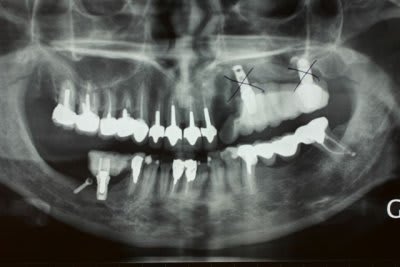

3 Radiographie Panoramique de la correction

4 Utilisation d'un implant à plaque.

La vis d'ostéosyntèse impossible à dévisser a dû être coupée.